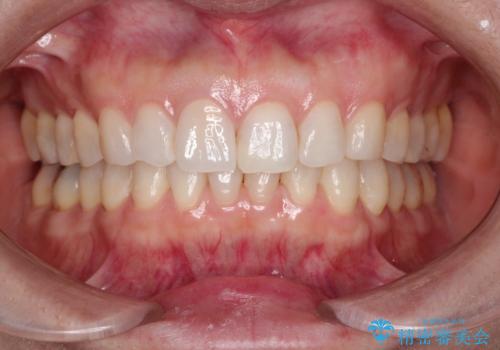

【オールセラミッククラウン】他院で入れた被せものがすぐとれる

- 「他院で治療した前歯の被せものが一か月の間に2回外れたのでやり変えたい」を主訴に来院されました。

10年前に根管治療を他院で行っており、根尖性歯周炎の予防のため根管治療から行いました。被せものはオールセラミッククラウンで治療を行いました。

ホワイトニングもご希望されたのでホームホワイトニングも行いました。

治療について

10年前にラバーダムシート無しに根管治療を行っており、現在、症状は出ていませんが、根尖性歯周炎の予防のため根管治療から行いました。ホームホワイトニングを2週間行って頂き、その後、オールセラミッククラウンで治療を行っています。